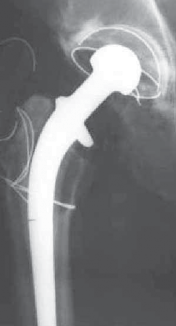

DEFINITION A fluted stem can be used to revise a loose femoral implant with one or more of the following: Cav…